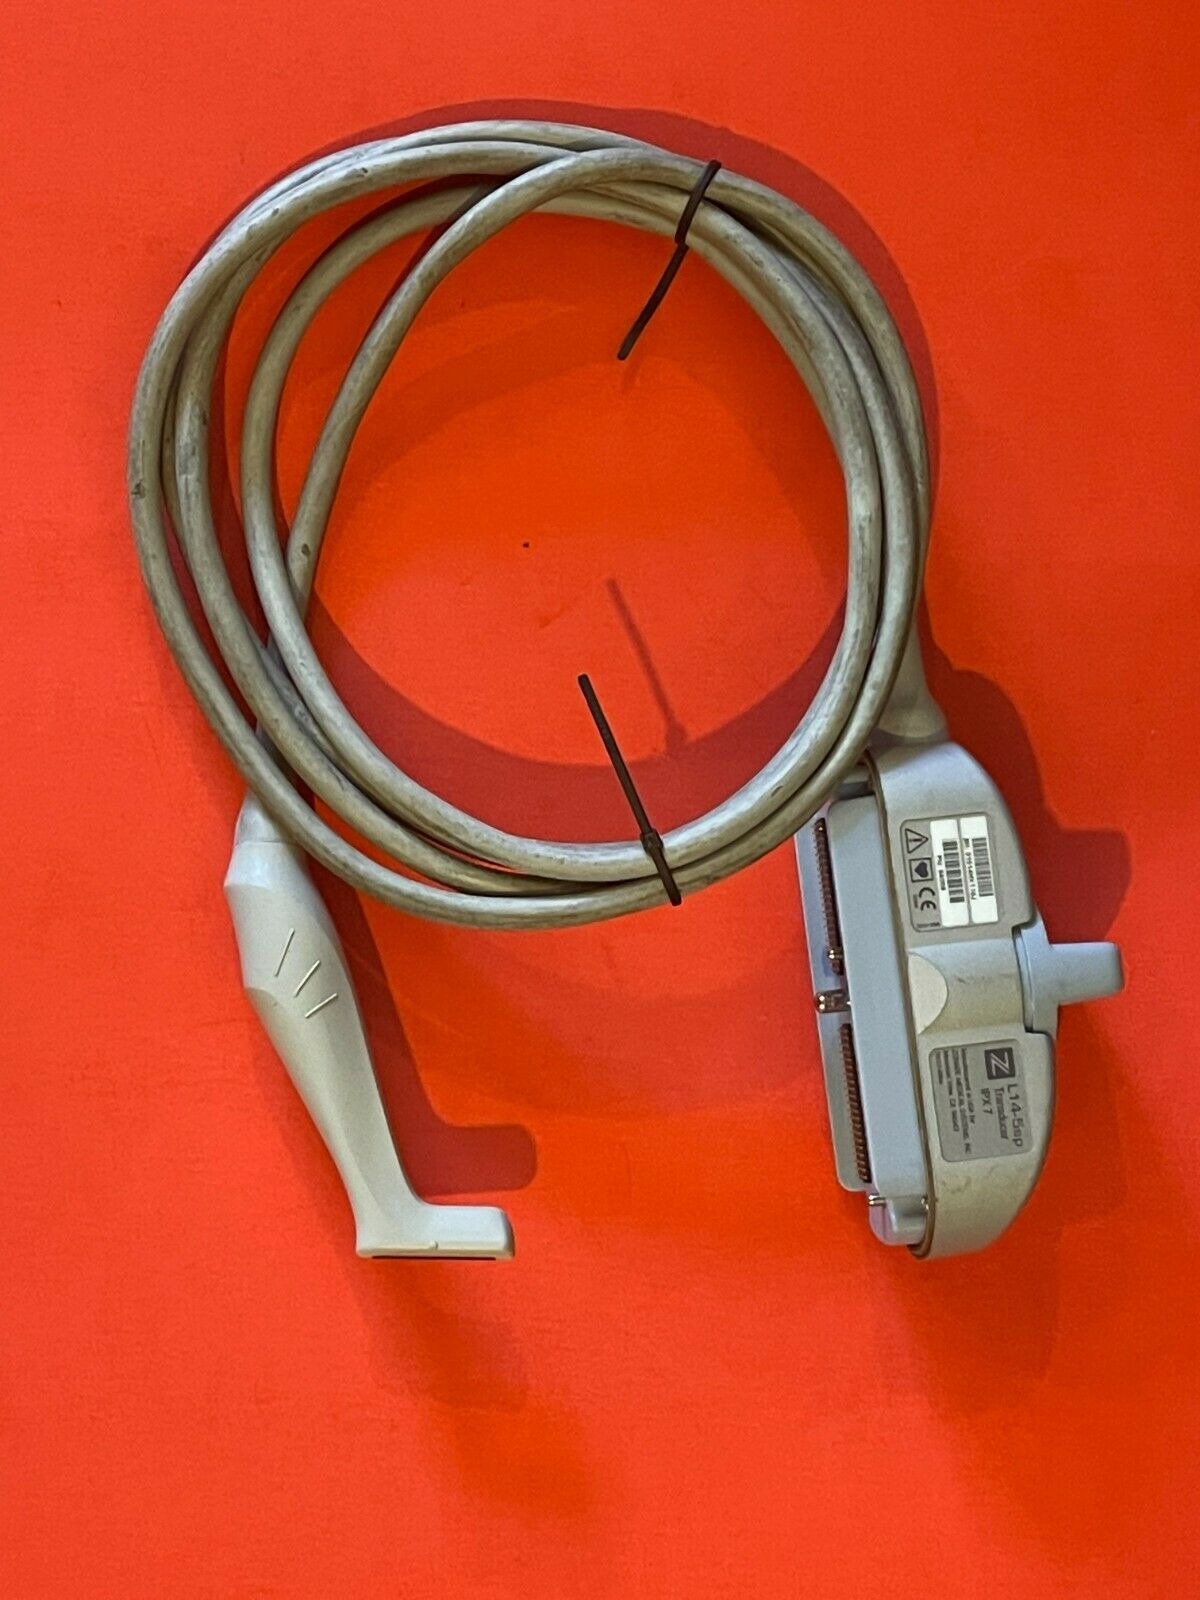

ZONARE L14-5SP IPX7 ULTRASOUND TRANSDUCER 84008

Sale price$ 306.68

Regular price$ 374.00